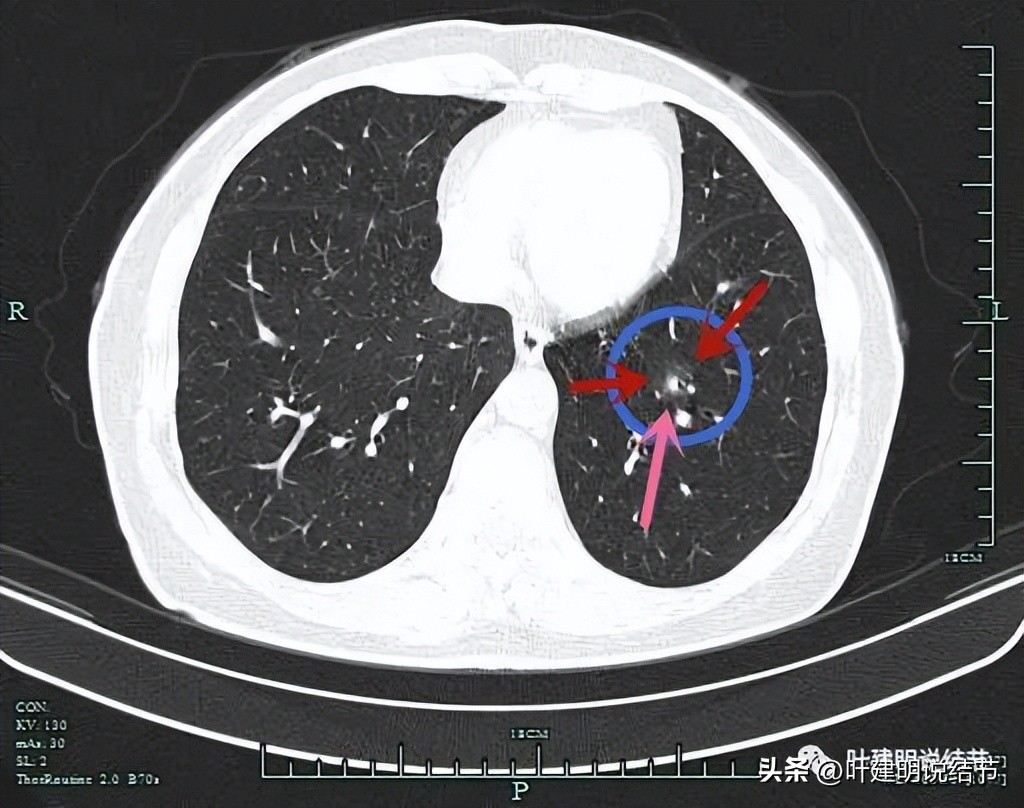

患者某C,女性,今年60岁,约1年前检查发现两肺多达15处以上的磨玻璃结节,分布于各个肺叶,其中右上叶最多,左下叶的最明显。而且还做过脑膜瘤手术,还有高血压等慢性病。下面这几处是左侧较为明显的病灶:

粉色圈起来的左上叶病灶(病灶A)密度低,但轮廓清楚,是肿瘤范畴的结节,但风险小;红色圈起来的左下叶结节(病灶B)虽然密度不太高,实性成分不明显,但它有多支微血管进入,而且紧贴胸膜,是要考虑微浸润性腺癌可能性为大的;蓝色圈起来的左下叶病灶(病灶C)是混合磨玻璃结节,但它的轮廓较为模糊,中间实性成分偏长方形,缺乏膨胀性或收缩力,磨玻璃部分密度过低,恶性的可能性虽有,但不如红色圈起来的病灶那么确定。而且与1年前对比,蓝色圈起来的这个病灶没有明显进展。此灶肉芽肿性炎的概率要高于恶性。